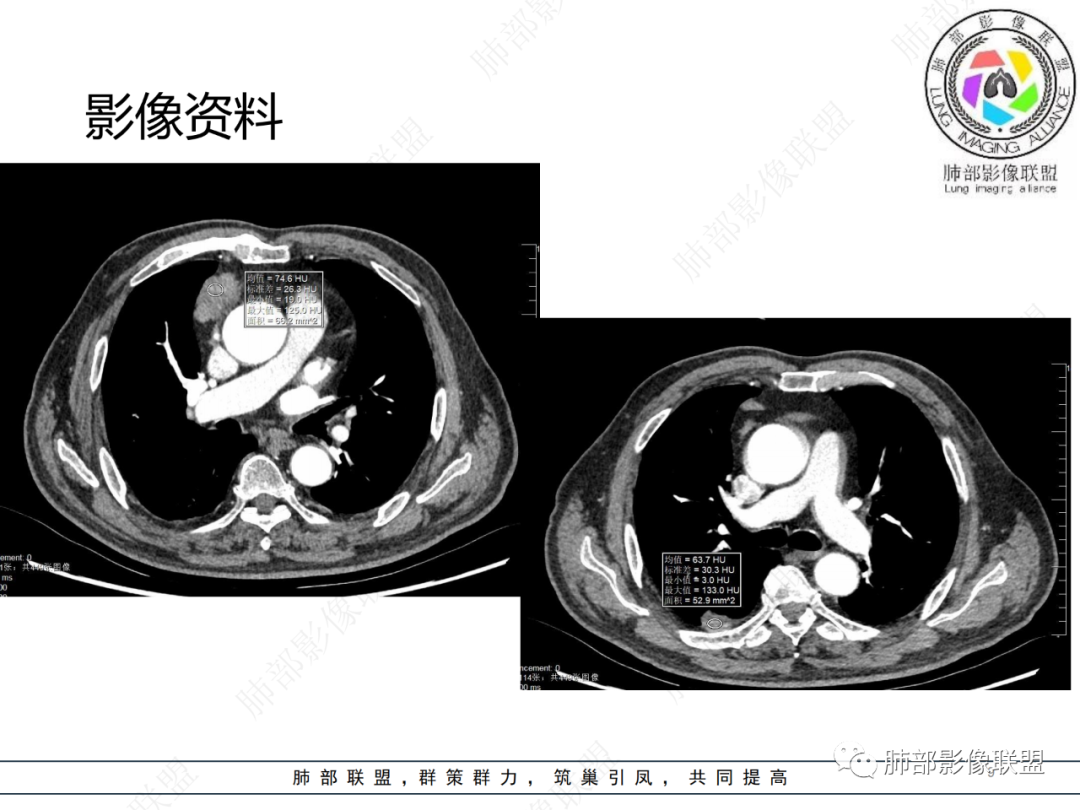

右前纵膈不规则软组织密度影,密度均匀,分叶,中度强化,心包受侵,右侧胸膜不规则结节,明显强化,考虑胸腺瘤B2或B3型伴胸膜转移,鉴别胸腺癌

老年男性,右前纵隔结节,右侧胸膜下小结节,增强前纵隔结节中度欠均匀性强化,首先考虑胸腺瘤(B2、3级),鉴别纵隔神经内分泌肿瘤,比如类癌。

男,76岁,前纵膈偏右结节,形态较规则,浅分叶,富血供,增强明显不均匀强化,强化峰值在动脉期,考虑B2,3胸腺瘤,鉴别胸腺类癌(一般强化峰值在静脉期),胸腺鳞癌(形态不规则,边缘不清晰,多侵犯邻近大血管)

肺盟病例,右前纵膈占位,边缘有钙化,强化显著,临近心包有少许积液。考虑胸腺类癌可能,右肺胸膜下病灶考虑炎性肉芽肿可能。